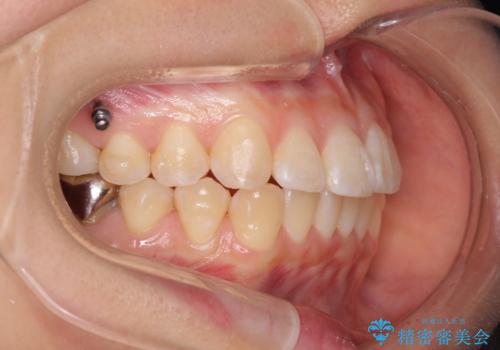

正中のズレ、引っ込んだ前歯の矯正

- 噛んだ時の前歯正中のズレ、引っ込んでいる前歯を治したい。と矯正治療を希望され来院されました。

左上2の前歯はスペースが足りないため、後方に引っ込んでしまっている状態です。

マウスピース矯正システムインビザラインで歯の後方移動、咬合関係の修正を行ったのち、引っ込んでいる左上2をワイヤーを用いて短時間で引き出す治療計画としました。

部分ワイヤー矯正を行なったことで約3ヶ月という短期間で前歯を綺麗に並べることができました。